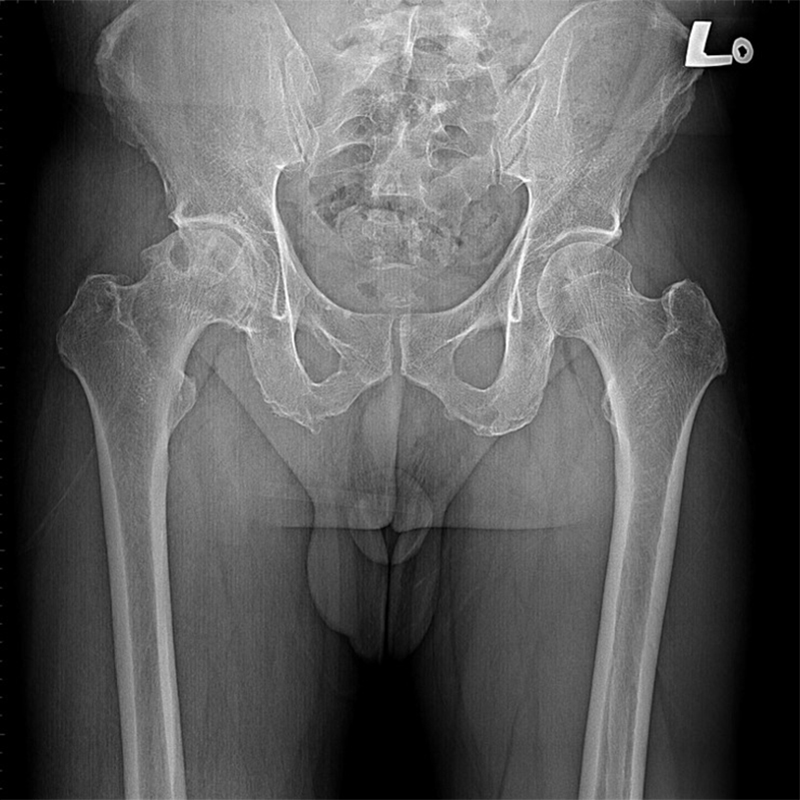

傳統髖關節置換 首頁 案例分享 髖關節手術 傳統髖關節置換 54歲蔡先生退化性關節炎 術前 術後 張女士 51歲 退化性關節炎(DDH先天發育不全 CROWE TYPE 2) 術前 術後 38歲林先生 退化性關節炎 術前 術後 72歲謝女士 退化性關節炎 術前 術後 71歲 謬女士 骨股頭壞死 術前 術後 50歲 郭先生骨股頭壞死 術前 術後 80歲 盧先生骨股頭壞死 術前 術後 林先生 37歲 術前 術後 邱女士 51歲 術前 術後 張女士 50歲 術前 術後